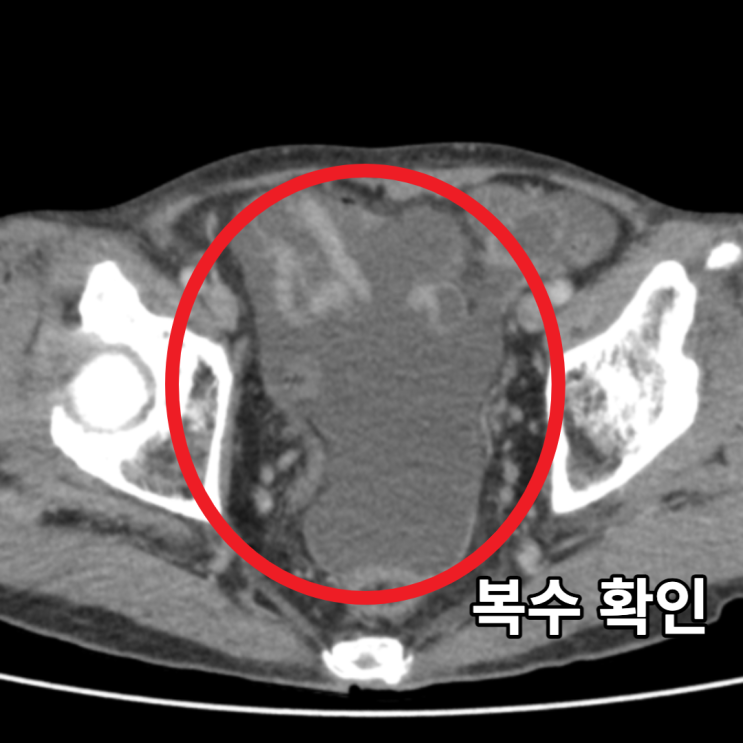

복강내 악성림프종으로 인한 복수가 차는 증상은 해당 종양이 복강 내에 위치하고 있어 종양이 증식하면서 복부의 부피가 증가하면서 발생합니다. 복수가 차면 복통, 복부팽창, 복부부종, 소화불량, 체중감소, 구역질, 위장장애, 소변 어려움 등의 증상이 나타날 수 있습니다.

혈액검사에서 큰 이상소견 보이지 않아, 추가로 CT 당일 시행하였습니다. 시행한 복부 CT상에서 불편감을 호소하시는 부위에 약 16cm 크기의 큰 종양이 확인되었으며, 주변 임파선 크기 증가 및 복수가 확인되어, 림프증식성 질환이나 육종등의 종양이 주변 임파선 및 복막으로 전이되었을 가능성이 확인되었습니다.

• 복부CT 횡단면: 복수 확인(빨간 동그라미) 복부CT 횡단면: 복수 확인(빨간 동그라미)